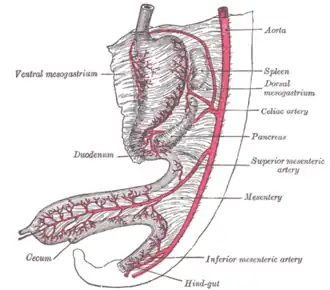

Surface projections of the major organs of the trunk, showing celiac artery in middle | |

The celiac (/ˈsiːli.æk/) artery (also spelled coeliac in British English), also known as the celiac trunk, Haller's tripod or truncus coeliacus, is the first major branch of the abdominal aorta. It is about 1.27 cm (half an inch) in length. Branching from the aorta at the level of the T12-L1 intervertebral disc in typical anatomy, it is one of three anterior/midline branches of the abdominal aorta (the others are the superior and inferior mesenteric arteries).

The celiac artery supplies oxygenated blood to the liver, stomach, abdominal esophagus, spleen, and the superior half of both the duodenum and the pancreas.[2] These structures correspond to the embryonic foregut. (Similarly, the superior mesenteric artery and inferior mesenteric artery feed structures arising from the embryonic midgut and hindgut respectively. Note that these three anterior branches of the abdominal aorta are distinct and cannot substitute for one another, although there are limited connections between their terminal branches.)

Abdominal part of digestive tube and its attachment to the primitive or common mesentery; human embryo at six weeks

Abdominal part of digestive tube and its attachment to the primitive or common mesentery; human embryo at six weeks -